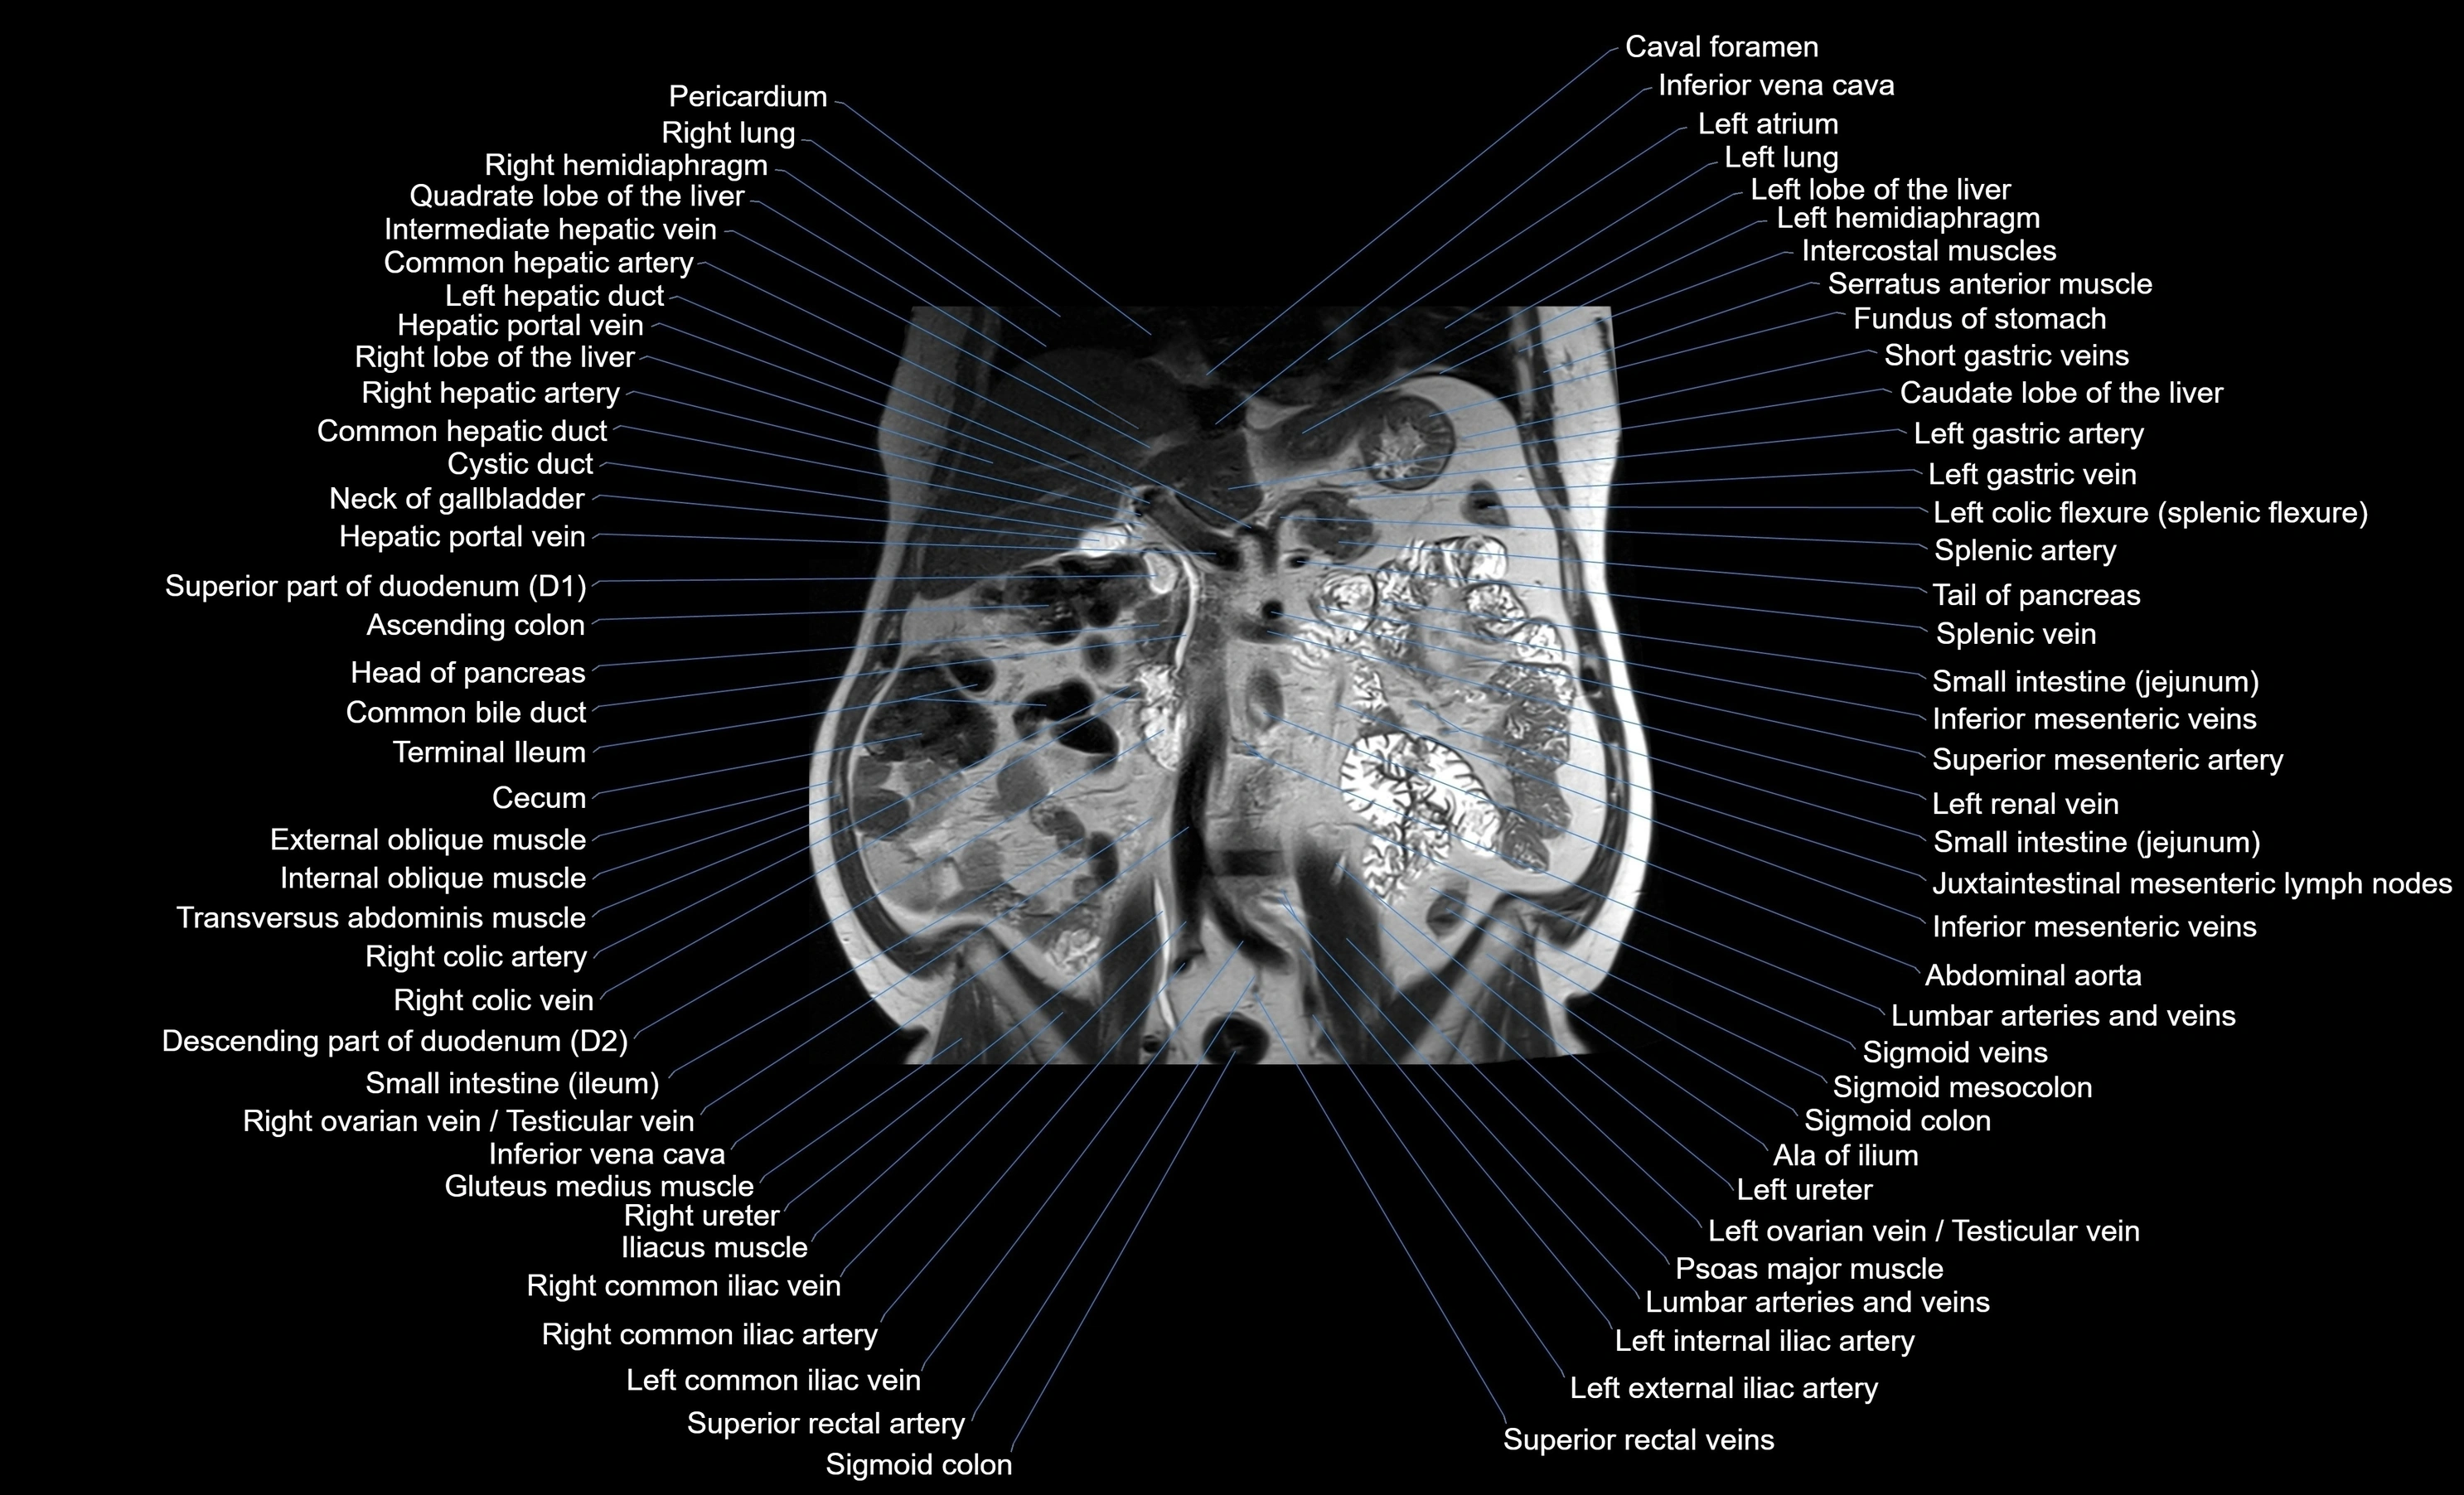

- Abdominal aorta

- Ascending colon

- Cecum

- Descending colon

- Duodenum – Descending part (D2)

- Head of pancreas

- Inferior mesenteric artery (IMA)

- Inferior vena cava

- Left ureter

- Right colic artery

- Sigmoid veins

- Superior mesenteric artery (SMA)

- Superior rectal artery

- Transverse colon